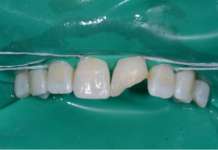

Restauri indiretti in composito fresato nel workflow digitale

Si documenta la gestione di un restauro indiretto di elemento 1.6 affetto da infiltrazione e frattura cuspidale, trattato con tecnica adesiva indiretta e supporto...